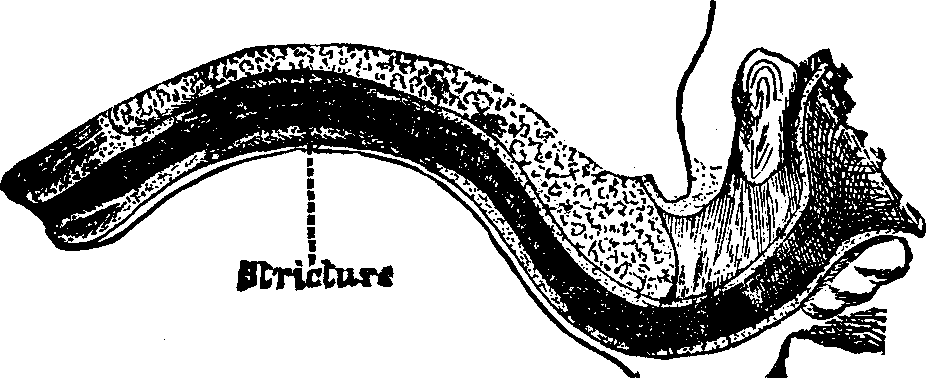

In the obstructive variety of dysmenorrhea, some organic impediment hinders the exit of the menstrual blood from the uterus, which, consequently, becomes distended and painful. The pain may be constant, but is most acute when the uterus makes spasmodic efforts to discharge the menstrual blood. If these efforts prove successful, there is an interval of relief. Flexion or version of the womb may produce partial occlusion of the canal of the neck of the uterus, thus preventing the free flow of the menstrual fluid through it. Tumors located in the body or neck of the uterus often cause obstruction to the free discharge of the menses. Imperforate hymen and vaginal stricture also sometimes cause obstruction and give rise to painful menstruation. As these several abnormal conditions and diseases will be treated of elsewhere in this volume, we omit their further consideration here.

Partial adhesion of the walls of the neck of the womb may result from inflammation of the mucous lining, and prevent a free and easy exit of the menstrual fluid. In many cases, the contracted and narrowed condition of the canal of the cervix seems to be a congenital deformity, for we can trace it to no perceptible cause. It is also true that contraction and partial, or even complete, stricture of the cervix, or neck of the womb, often results from the improper application of strong caustics to this passage by incompetent and ignorant surgeons. Every person has observed the contraction of tissue caused by a severe burn, which often produces such a distortion of the injured part as to disfigure the body for life. A similar result is produced when the neck of the womb is burned with strong caustics. The tissues are destroyed, and, as the parts heal, the deeper-seated tissues firmly contract, forming a hard, unyielding cicatrix, thus constricting the [pg 695]neck of the womb, through which the menses pass into the vagina.

Treatment. From the nature of this malady, it will readily be seen that no medical treatment can effect a radical cure. We must therefore resort to surgery. In a small proportion of cases, the stricture may be cured by repeated dilations of the constricted part of the cervical canal. This may be accomplished by using a very smooth probe which is fine at the point, but increases in size, so that its introduction will widen and expand the orifice and canal. The stricture may be overcome in many cases by using different sized probes. In some instances, we have employed the uterine dilator, represented by Fig. 3. We have also introduced sea-tangle and sponge tents into the neck of the womb, and allowed them to remain until they expanded by absorbing moisture from the surrounding tissues. The latter process is simple, and in many cases preferable. By means of a speculum (see Figs. 15 and 16), the mouth of the womb is brought into view, and the surgeon seizes a small tent with a pair of forceps and gently presses it into the neck of the womb, where it is left to expand and thus dilate the passage. If there seems to be a persistent disposition of the circular fibers of the cervix to contract, and thus close the canal, a surgical operation will be necessary to insure permanent relief. In performing this operation, we use a cutting instrument called the hysterotome (see Figs. 4 and 5). By the use of this instrument, the cervical canal is enlarged by an incision on either side. The operation is but slightly painful, and, in the hands of a competent surgeon, is perfectly safe. We have operated in a very large number of cases and have never known any alarming or dangerous symptoms to result. After the incision, a small roll of cotton, thoroughly saturated with glycerine, is applied to the incised parts, and a larger roll is introduced into the vagina. The second day after the operation, the cotton is removed, the edges of the wound separated by a uterine sound or probe, and a cotton tent introduced into the cervix, and allowed to remain, so that it will expand and thus open the wound to its full extent. This treatment must be thoroughly applied, and repeated every alternate day, until the incised parts are perfectly healed.